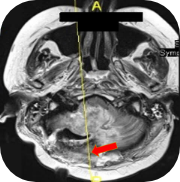

Fatima's repeat cerebral CT showed

enlargement of the mass and complete

obliteration of the fourth ventricle.

Cerebellitis–encephalitis involving all of

the right (and a large portion of the left)

cerebellar vermes and the base of the

right occipital lobe was also seen

Images supplied with permission of treating clinician.